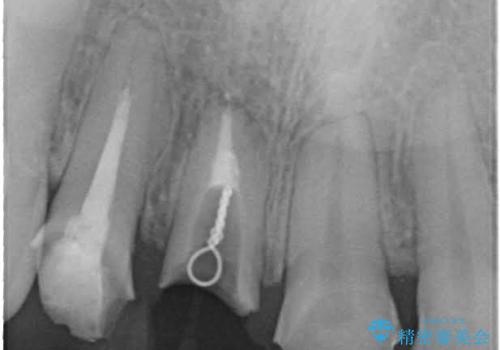

- 抜歯前提の歯根挺出により保存の難しい前歯を抜去

→根管治療のやり直しなどを経て、ブリッジを製作する。

古いかぶせ物は土台ごと歯から脱落してしまっており、歯の内面には複数の亀裂が入っている状態でした。残存歯質が非箔であることと、動揺の程度から、やむを得ず抜歯→ブリッジという方法を選択していただき、歯根挺出を用いることでなるべく前歯の骨の陥没を防ぎ、ブリッジを製作しました。